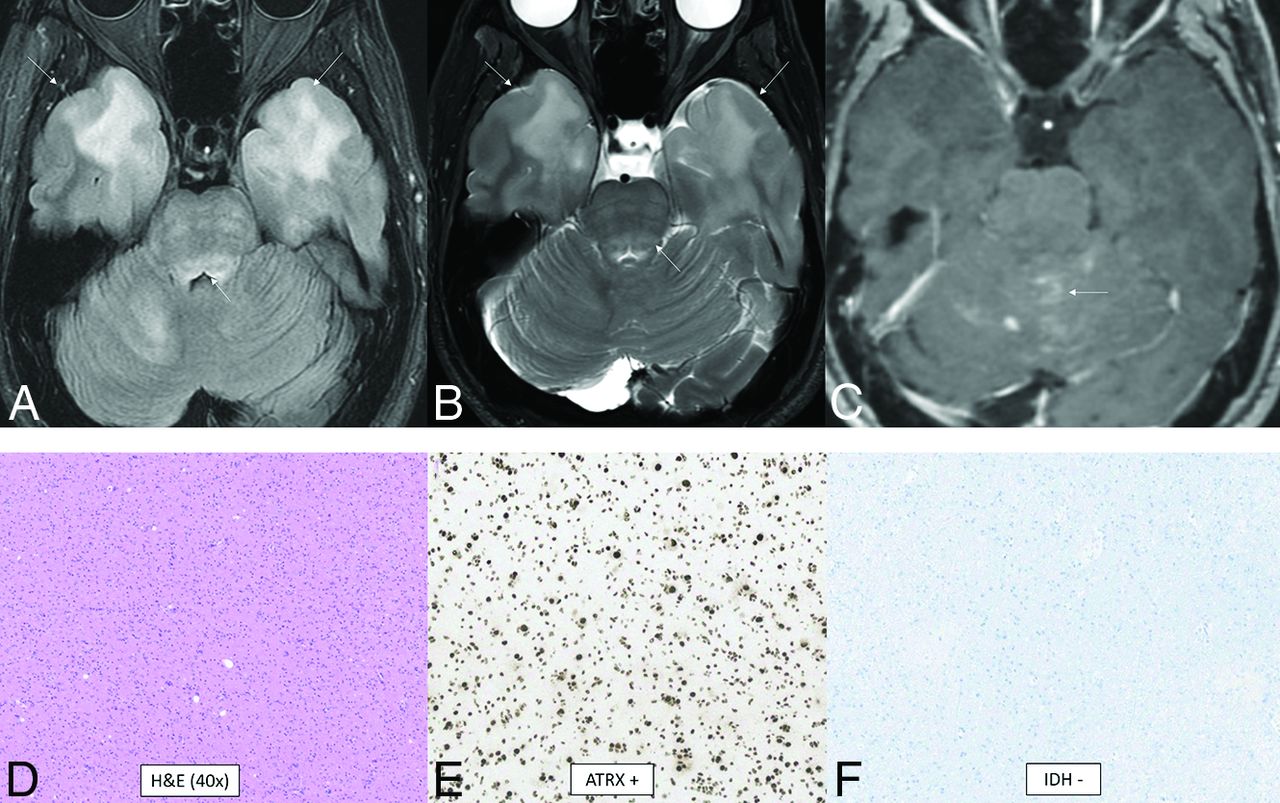

Diffuse Pediatric-Type High-Grade Glioma, H3 Wild-Type and IDH Wild-Type

Diffuse pediatric-type high-grade glioma is another of the 4 pediatric high-grade glioma types. It does not have an assigned WHO grade or a single defining molecular or genetic feature.1 About half of tumors previously classified as “pediatric glioblastoma” demonstrate mutations of histone 3 or uncommonly IDH1/2. The remaining heterogeneous tumors now fall under this new classification. The 3 recognized subtypes are characterized by MYCN, PDGFRA, and EGFR amplifications with numerous coexisting genetic abnormalities described.24 The MYCN subtype has high cellularity and mitosis, spindle, and epithelioid cell components; necrosis; and microvascular proliferation.25,26 The median age at diagnosis is 8–11 years (range, 2–18 years).24 There is no sex predilection overall, but there is a slight male predominance for the EGFR subtype (male/female ratio, 1.6:1).24 The location is usually supratentorial, with the posterior fossa approaching 20% of cases, depending on subtype.24 The MYCN subtype classically shows a solid, enhancing, diffusion-restricting, well-marginated temporal lobe mass abutting the meninges with tumoral necrosis, rare hemorrhage, and no calcifications.25,26 A tumor in the pons has greater enhancement and diffusion restriction compared with a diffuse midline glioma, H3 K27-altered.25 Figure 5 demonstrates a less-typical case without enhancement of the primary tumors.

Diffuse pediatric-type high-grade glioma, H3 wild-type and IDH wild-type. MR images demonstrate diffusely infiltrating masses in the bilateral temporal lobes with mild mass effect, T2-FLAIR (A) and T2-hyperintensity (B, anterior arrows), and no enhancement (C). There is additional T2-FLAIR and T2-hyperintensity in the dorsal pons and posterior fossa leptomeningeal enhancement (posterior arrows). Histology reveals a high-grade diffusely infiltrating astrocytoma with high mitotic activity (D). The tumor shows ATRX retention (E) and wild-type IDH status (F) on immunohistochemical stains. Whole-genome methylation analysis showed a match to diffuse pediatric-type high-grade glioma. The tumor was H3 wild-type and IDH wild-type and had a TERT promoter mutation, which was identified on the neuro-oncology targeted next-generation sequencing panel.